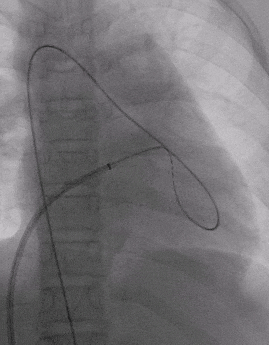

锁定与牵拉试验

释放封堵器

释放后超声

超声下可见室水平和房水平都无残余分流